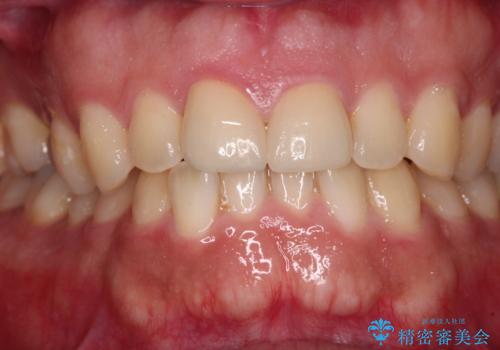

仮歯に置き換え、しみる感覚が改善されてことを確認された後に、オールセラミッククラウンにて補綴治療を行うこととしました。

術後の経過は良好でしたが、レントゲン写真にて神経が失活している時に認められる透過像のようなものが見られました。

神経の反応はあるので失活していないようですが、時間が経過すると衝撃による失活が起こることもあるため、定期的な経過観察が必要です。